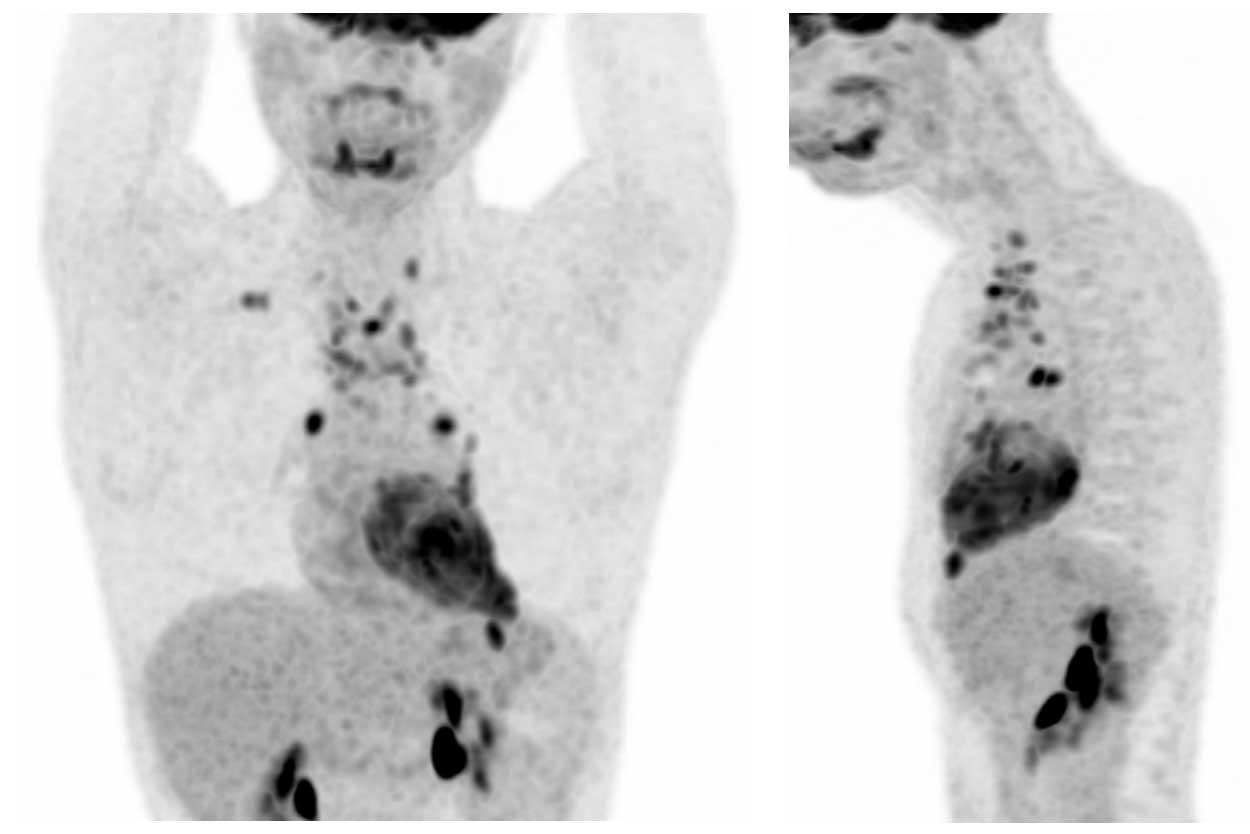

Ca lâm sàng

Các hình ảnh này của một bệnh nhân nam 36 tuổi bị hội chứng Cushing, đã được phẫu thuật cắt bỏ u tuyến yên.

Tuy nhiên, hội chứng Cushing vẫn tồn tại và phát hiện một khối ở trung thất.

Hình ảnh

Khối đặc với vôi hóa trung tâm (mũi tên đen).

Lưu ý bờ khối không đều ở phía bên trái.

Hạch bạch huyết thượng đòn trái to (hạch Virchow: mũi tên trắng).

Đây không phải là PET-CT thông thường mà là PET Dotatoc, được sử dụng để phát hiện u thần kinh nội tiết và các tổn thương di căn của chúng.

Có nhiều tổn thương di căn xương (mũi tên).

Chẩn đoán cuối cùng

U thần kinh nội tiết tuyến ức (NETT)

U thần kinh nội tiết tuyến ức là các u hiếm gặp.

Chúng có tính chất rất xâm lấn và thường biểu hiện với sự xâm lấn các cấu trúc trung thất xung quanh, đồng thời liên quan đến các bệnh lý nội tiết như hội chứng Cushing, to đầu chi (acromegaly) và hội chứng MEN-1.